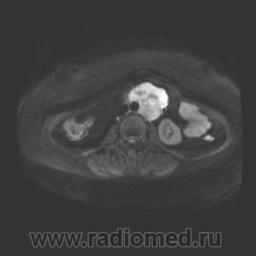

Прошу высказать мнение по поводу представленного случая. Пациент направлен для уточнения характера образования, обнаруженного на УЗИ.

Диффузионно-взвешенные изображения:

Очаг в селезенке и забрюшинное парааортальное образование. Что это? Лимфома? МРщики, просветите.

Да, так выглядит лимфома (скорее всего, неходжкинская).

Помимо очага в селезенке есть еще изменения в теле позвонка S1.